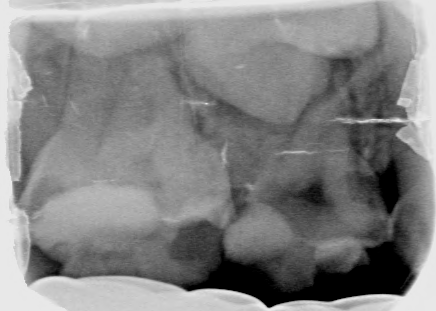

Afbeelding 3a: Röntgenfoto's op de leeftijd van 6 jaar, juli 2018.

Afbeelding 3b: Röntgenfoto's op de leeftijd van 6 jaar, juli 2018.

Afbeelding 3c: Röntgenfoto's op de leeftijd van 6 jaar, juli 2018.

Afbeelding 3d: Röntgenfoto's op de leeftijd van 6 jaar, juli 2018.

Jenny is 6 jaar. Er worden röntgenopnames en kleurenfoto’s gemaakt (Afb. 3 en 4). Op de röntgenfoto’s lijken de bovenmolaren ernstig aangetast, maar ze zijn hard en inactief. De niet-gerestaureerde bovenmolaren en kronen met gerestaureerde ondermolaren zijn vrij van ontsteking. Jenny kwam voor mondonderzoek om de 4-6 mnd.

Voor het maken van röntgenfoto’s werd een doormidden geknipt maat 0 fosforplaatje gebruikt. Maat 0 is voor veel jonge kinderen te groot en moeilijk te accepteren.